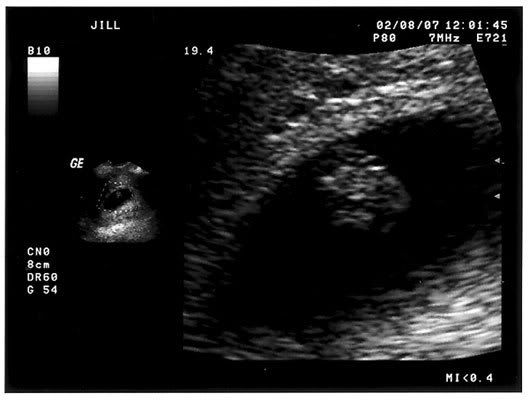

Here's the u/s pic from baby's first photo session - LOVE that blob! The hb measured 125 bpm and the tech said that was perfect for how far along I am.